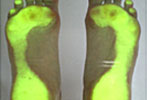

Korrektur der Fußfehlstellung

zu Behandlungsbeginn

nach 12 Monaten Behandlung

nach 24 Motanten Behandlung

Wer die Abdrücke seiner bloßen nassen Füße auf trockenem Fußboden oder als Sandabdruck betrachtet, wird feststellen, dass es zwischen rechtem und linkem Abdruck Unterschiede gibt. Das ist ein Beleg für ein Ungleichgewicht des Körpers.